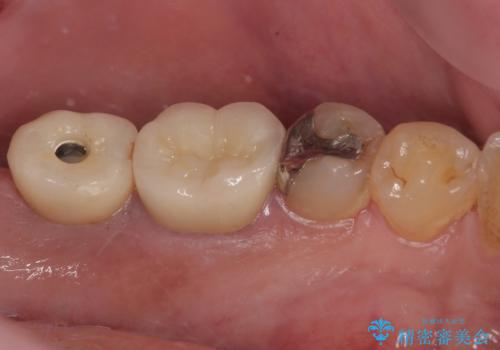

- 以前、咬合力の強さで歯の神経が失活してしまい、当院にて根管治療を行った患者様ですが、今度は咬合力の影響で歯根が破折してしまった患者様です。

歯根が破折してしまった歯は抜歯が必要となり、特に咬合力が強い方ですと、インプラント治療による治療がお勧めとなります。

咬合力の影響で歯が壊れてしまう方の場合、長期間欠損が続くと、連鎖するように他の歯が壊されてしまうリスクがあるため、抜歯即時インプラントにより、治療期間の短縮を図ることとしました。

治療は順調に進み、わずか3ヶ月でセラミッククラウンを装着することができました。

他の歯への影響もなく、無事に治療を終えることができました。